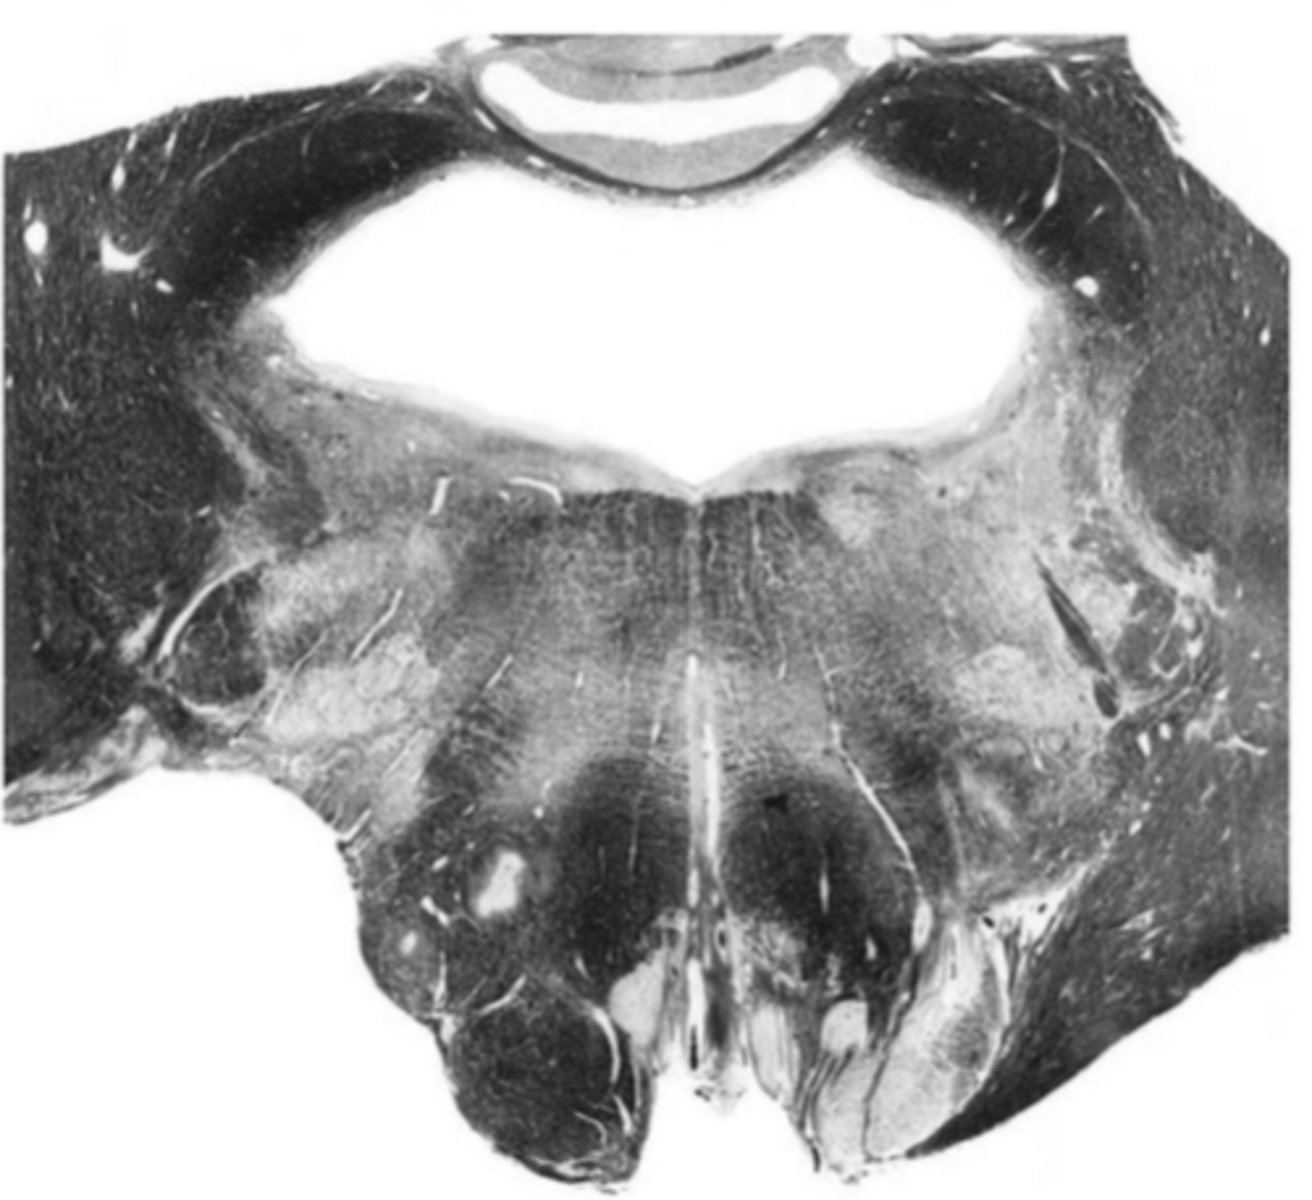

closed medulla

ID the brainstem level

central canal

ID the space

central gray

ID the structure

hypoglossal nucleus

ID the nucleus

gracile nucleus

cuneate nucleus

inferior cerebellar peduncles

reticular formation

internal arcuate fibers

ID the fibers

principle olivary nucleus

medial lemniscus

corticospinal fibers

anterior median sulcus

posterior median sulcus

posterior intermediate sulcus

ID the light area

cuneate fasciculus

ID the dark area

gracile fasciculus

posterior lateral sulcus

spinal accessory nucleus

descending motor pathways

motor decussation